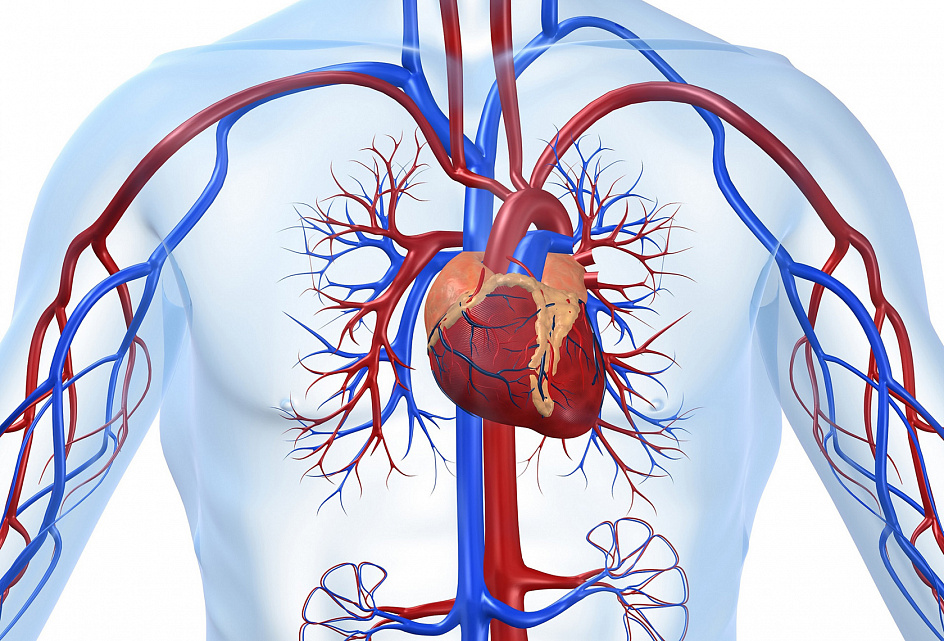

Кровеносная система

Кровеносная система – одна из основных человеческих систем.

Система кровообращения представлена :

— Сердцем;

— Кровеносными сосудами;

— Кровью.

Сердце – это, так называемый, насос, который качает кровь, в одном направлении, по кровеносной сети. Длина кровеносных сосудов в человеческом организме составляет около 150 тысяч километров, каждый из которых выполняет индивидуальную функцию.

Крупные сосуды системы кровообращения :

— Яремная вена;

— Подключичная вена;

— Аорта;

— Легочная артерия;

— Бедренная вена;

— Сонная артерия;

— Верхняя полая вена;

— Подключичная артерия;

— Легочная вена;

— Нижняя полая вена;

— Бедренная артерия.

Кровеносная система человека

Кровь – это одна из базовых жидкостей человеческого организма, благодаря которой органы и ткани получают необходимое питание и кислород, очищаются от токсинов и продуктов распада. Эта жидкость может циркулировать в строго определённом направлении благодаря системе кровообращения. В статье мы поговорим о том, как устроен этот комплекс, благодаря чему поддерживается ток крови, и каким образом система кровообращения взаимодействует с другими органами.

Сердечно-сосудистый комплекс

Система, включающая сердце и все сосуды, начиная с самых крупных и заканчивая микроскопическими капиллярами диаметром в несколько микрон, обеспечивает циркуляцию крови внутри организма, питая, насыщая кислородом, витаминами и микроэлементами и очищая от продуктов распада каждую клеточку человеческого тела. Эту гигантскую по площади сложнейшую сеть нагляднее всего демонстрирует анатомия человека в картинках и схемах, поскольку теоретически разобраться, как и куда ведёт каждый конкретный сосуд, практически нереально — их количество в организме взрослого достигает 40 млрд и более. Тем не менее, вся эта сеть является сбалансированной замкнутой системой, организованной в 2 круга кровообращения: большой и малый.

В зависимости от объёма и выполняемых функций сосуды можно классифицировать следующим образом:

«Двигателем» столь крупной замкнутой сети является сердце — полый мышечный орган, благодаря ритмичным сокращениям которого кровь продвигается по сосудистой сетке. При нормальной работе каждую минуту сердце перекачивает не менее 6 литров крови, а за день — примерно 8 тысяч литров. Неудивительно, что сердечные заболевания являются одними из самых серьёзных и распространённых, — с возрастом этот биологический насос изнашивается, поэтому необходимо тщательно отслеживать любые изменения в его работе.